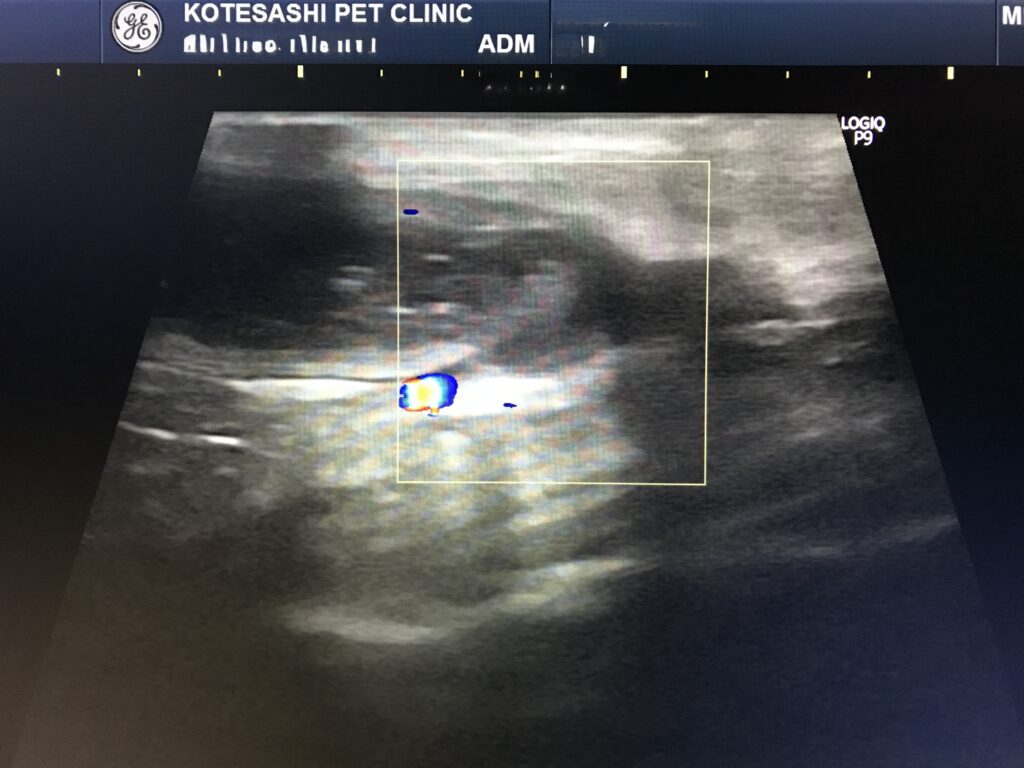

⬇️2年前、頻回嘔吐と食欲減退で来院いただいた際のエコー画像です。

消化管に液体が溜まっている部分と、狭窄(通過障害を起こしている)している部分がありました。

狭窄部位を手術で切除し、残った消化管を繋いで手術は終了しました。病理検査結果は『リンパ腫』。

エコー検査で消化管にシコリを認め、リンパ腫の再発と判断